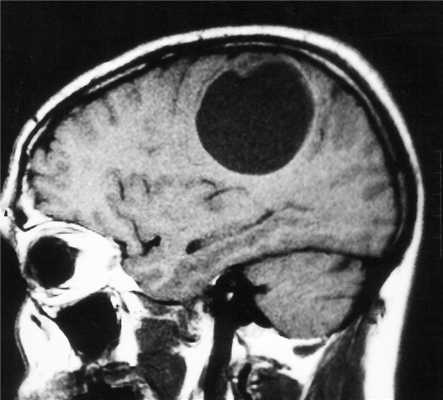

МРТ головного мозга. Множественная анапластическая астроцитома (стрелки). Сагиттальная Т1-зависимая МРТ с контрастированием.